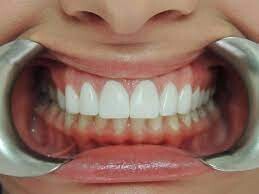

If you’re experiencing shrinking gums or tooth sensitivity while brushing and flossing your teeth, it could be due to receding gums. Also called gum or gingival recession, receding gums can’t grow back, but there are ways to catch the problem early and prevent your gums from getting worse. This article will discuss the causes, symptoms, treatment and how to prevent receding gums.

Receding gums are best avoided for several good reasons. Gum recession can lead to tooth sensitivity and even affect your smile, but that’s not all. Your gums (or gingiva) are critical in protecting the bone that holds your teeth in place. If the gums begin to shrink away, tooth roots can be exposed. Tooth roots can be more easily worn away than enamel covered surfaces and are susceptible to decay.